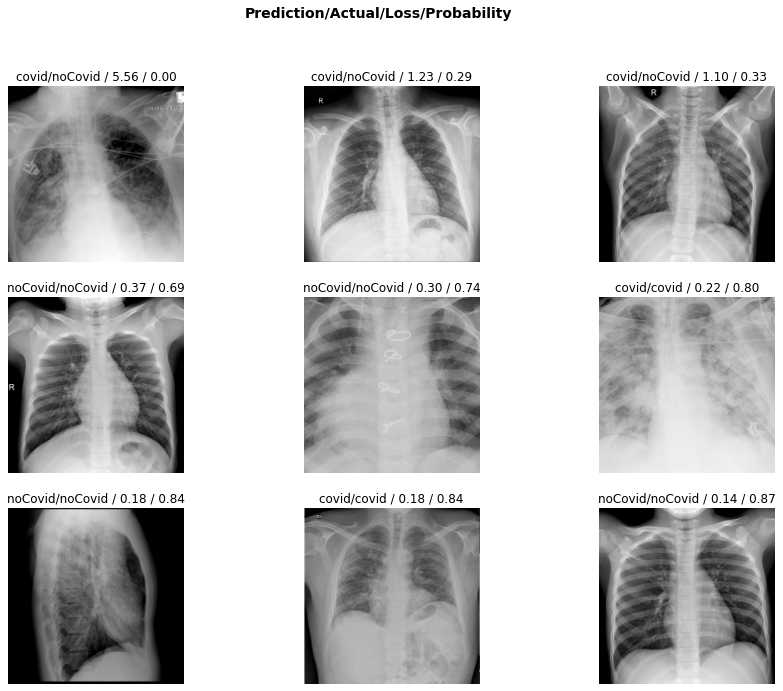

Pdf Deteccion Del Covid 19 Con Tecnicas De Deep Learning

Deteccion De Covid 19 En Imagenes De Rayos X Con Keras Tensorflow Y Deep Learning By Datacampero Medium

Detector De Covid 19 Usando Imagenes De Rayos X By Christian Tutiven Galvez Saturdays Ai Medium